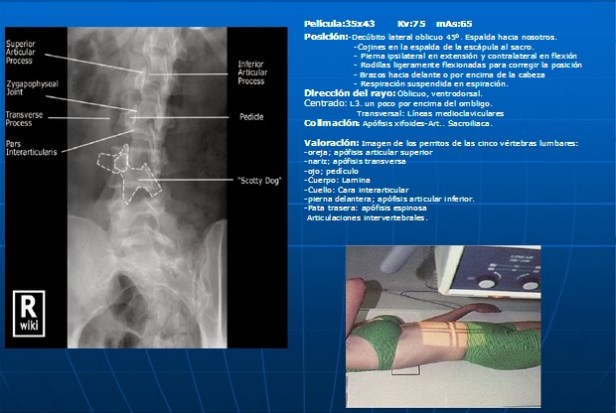

La identificación del perfil de un scottishdog (o proyección del Perrito, o también conocida como Proyección de La Chapelle) en una Radiografía de Columna Lumbar – en posición oblicua del paciente, en bipedestación – es un habitual procedimiento que los Técnicos Radiólogos suelen tener que comprobar para que se pueda ver la porción interarticular especialmente para diagnosticar la espondilolisis o espondolilostesis.

El Signo del Perro Escocés (Scotty dog sign) se refiere a la apariencia normal de los elementos posteriores de la columna lumbar cuando se ven en las proyecciones oblicuas:

- la apófisis transversa (la nariz)

- el pedículo (el ojo)

- la faceta articular inferior (la pata delantera)

- la faceta articular superior (que representa el oído)

- la porción interarticular o la lámina entre las facetas (equivalentes al cuello).

Obtención de la proyección